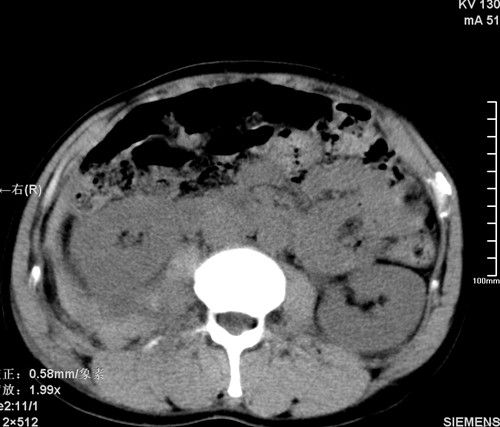

以下是引用qiushi在2008-3-28 12:00:00的发言:[br]腹膜后血肿,所见腰椎横突骨折.[br]建议上传骨窗、腰椎扫描.

以下是引用tao772在2008-3-28 12:29:00的发言:[br]右侧腹膜后积血,右侧腰大肌挫伤,右侧部分横突骨折. 肾脏最好报一下挫伤,必要时增强。